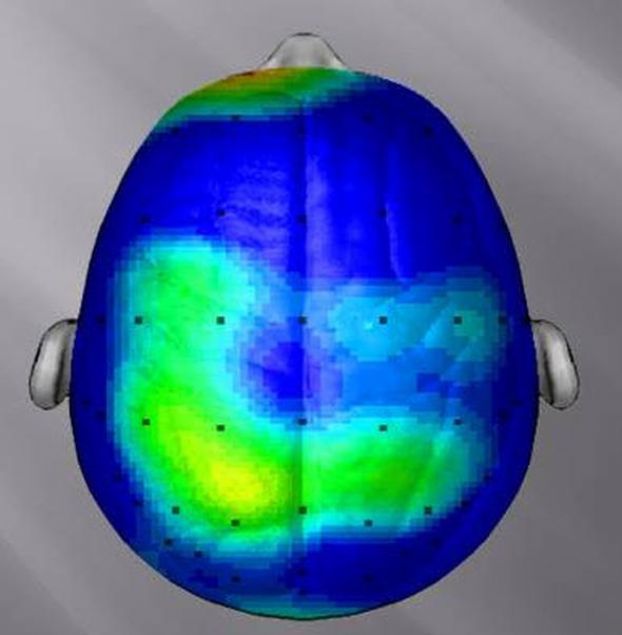

Otururken beyin aktivitemiz...